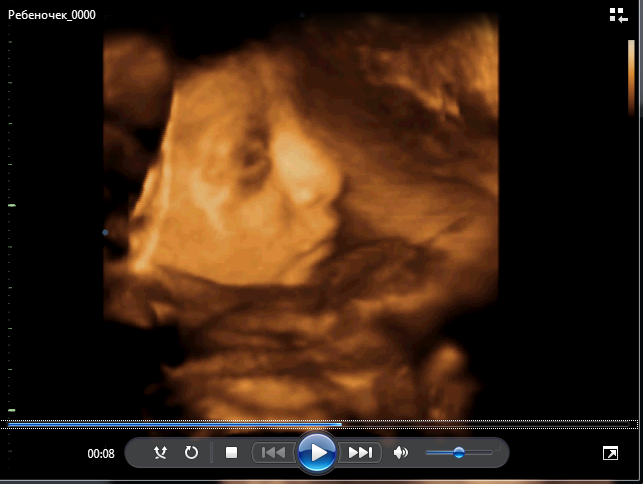

Нам записали диск с видео, правда всего два маленьких видео, т.к. Георгий парень не показушный, отвернулся и все!!!

Но как же он похож на мужа. это просто обалдеть! Вот правда, лежу, смотрю на экран телика и мысли в голове " во мне маленький муж, во мне маленький муж..." даже жутковато немного стало...

И еще он очень мило улыбался)

А вот и наш мини клон)

(Егор, 32 недели ровно)